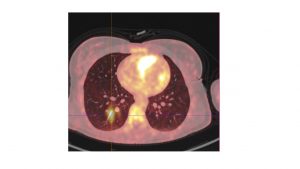

• une lésion nodulaire intraventriculaire droite hypermétabolique compatible avec un thrombus

• plage hypermétabolique pulmonaire lobaire inférieure droite de topographie vasculaire évoquant un processus embolique

Embolie pulmonaire lobaire inférieure droite avec thrombus intra ventriculaire droit.